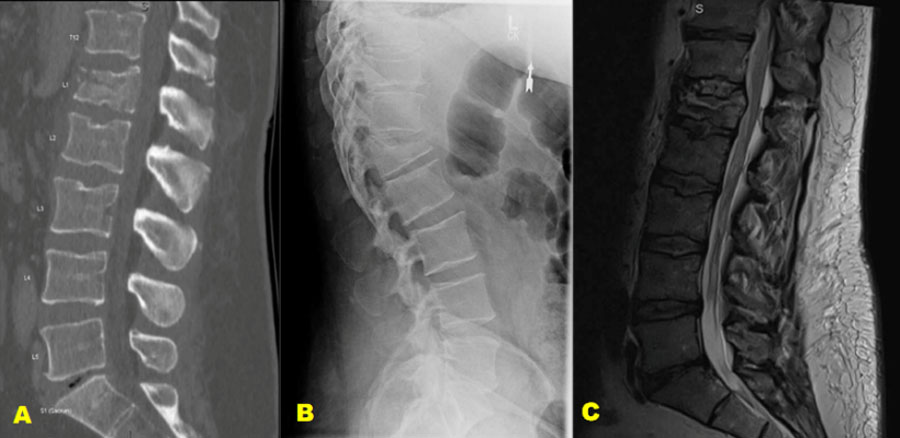

Example case 1: neurologically intact patient

Figure 1. A 45-year-old male who was involved in a motor accident and was ejected from the vehicle. The patient was neurologically intact.